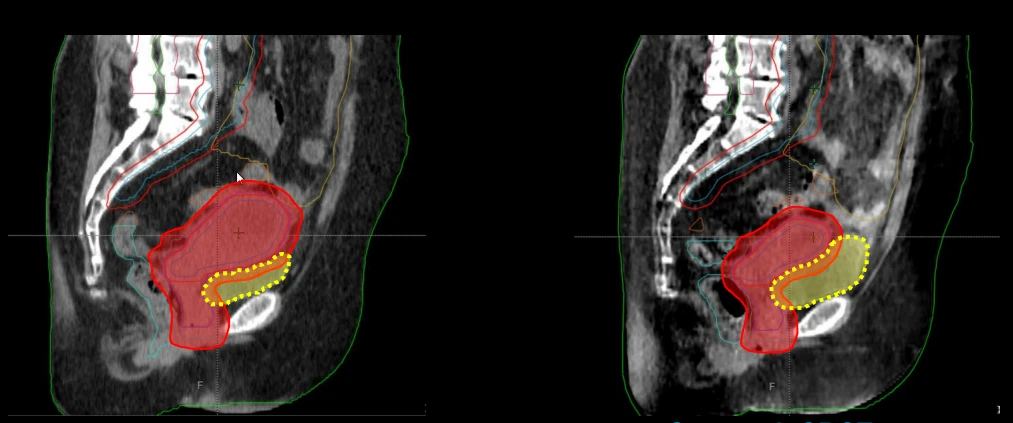

The third place case report, submitted by Amsterdam UMC, explored the potential of daily oART for bladder cancer to limit high-dose exposure of healthy tissue, compared to conventional non-adaptive radiotherapy. The paper examines a bladder cancer patient treated after cystoscopic tumor resection to 40 Gy in 20 sessions, with a simultaneous boost of 15 Gy to the tumor bed. By utilizing daily online adaptation of the treatment plan, the team was able to achieve smaller planning target volume margins. This reduced the dose to normal healthy tissues in the bladder and bowel, while maintaining 100% coverage of the target region.